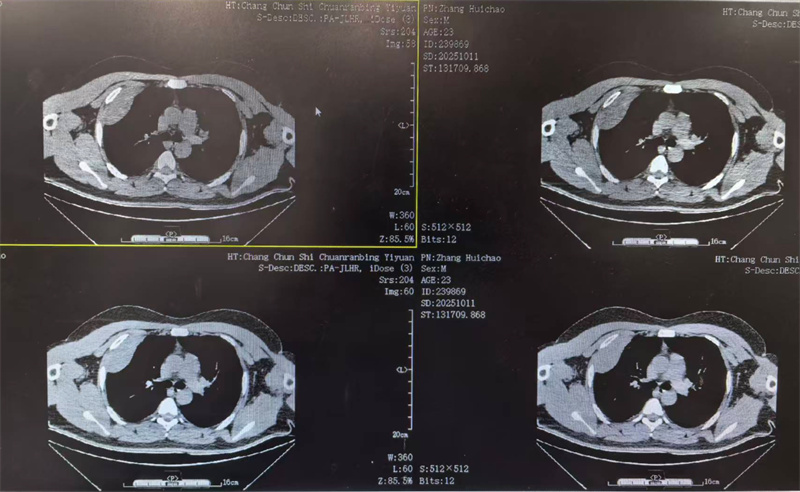

四个月前,23岁的小雨(化名)因胸闷前往医院就诊,CT检查结果显示右侧胸腔靠上位置出现包裹性脓胸,并进行穿刺检查,最终确诊为结核性包裹性脓胸,这个消息让小雨和家人陷入了深深的焦虑之中。

看着日益憔悴的小雨,医生建议手术治疗。术前,田子刚主任和宋巍峰医生在全面评估了小雨各项指标后,确定符合手术标准,便与麻醉科以及护理团队紧密配合,为小雨实施胸腔镜下胸膜剥脱术。

手术室内,胸腔镜在田子刚主任和宋巍峰医生紧密配合操控下,通过小小的切口精准插入小雨体内。在高清显示屏上,胸腔内的情况清晰可见。